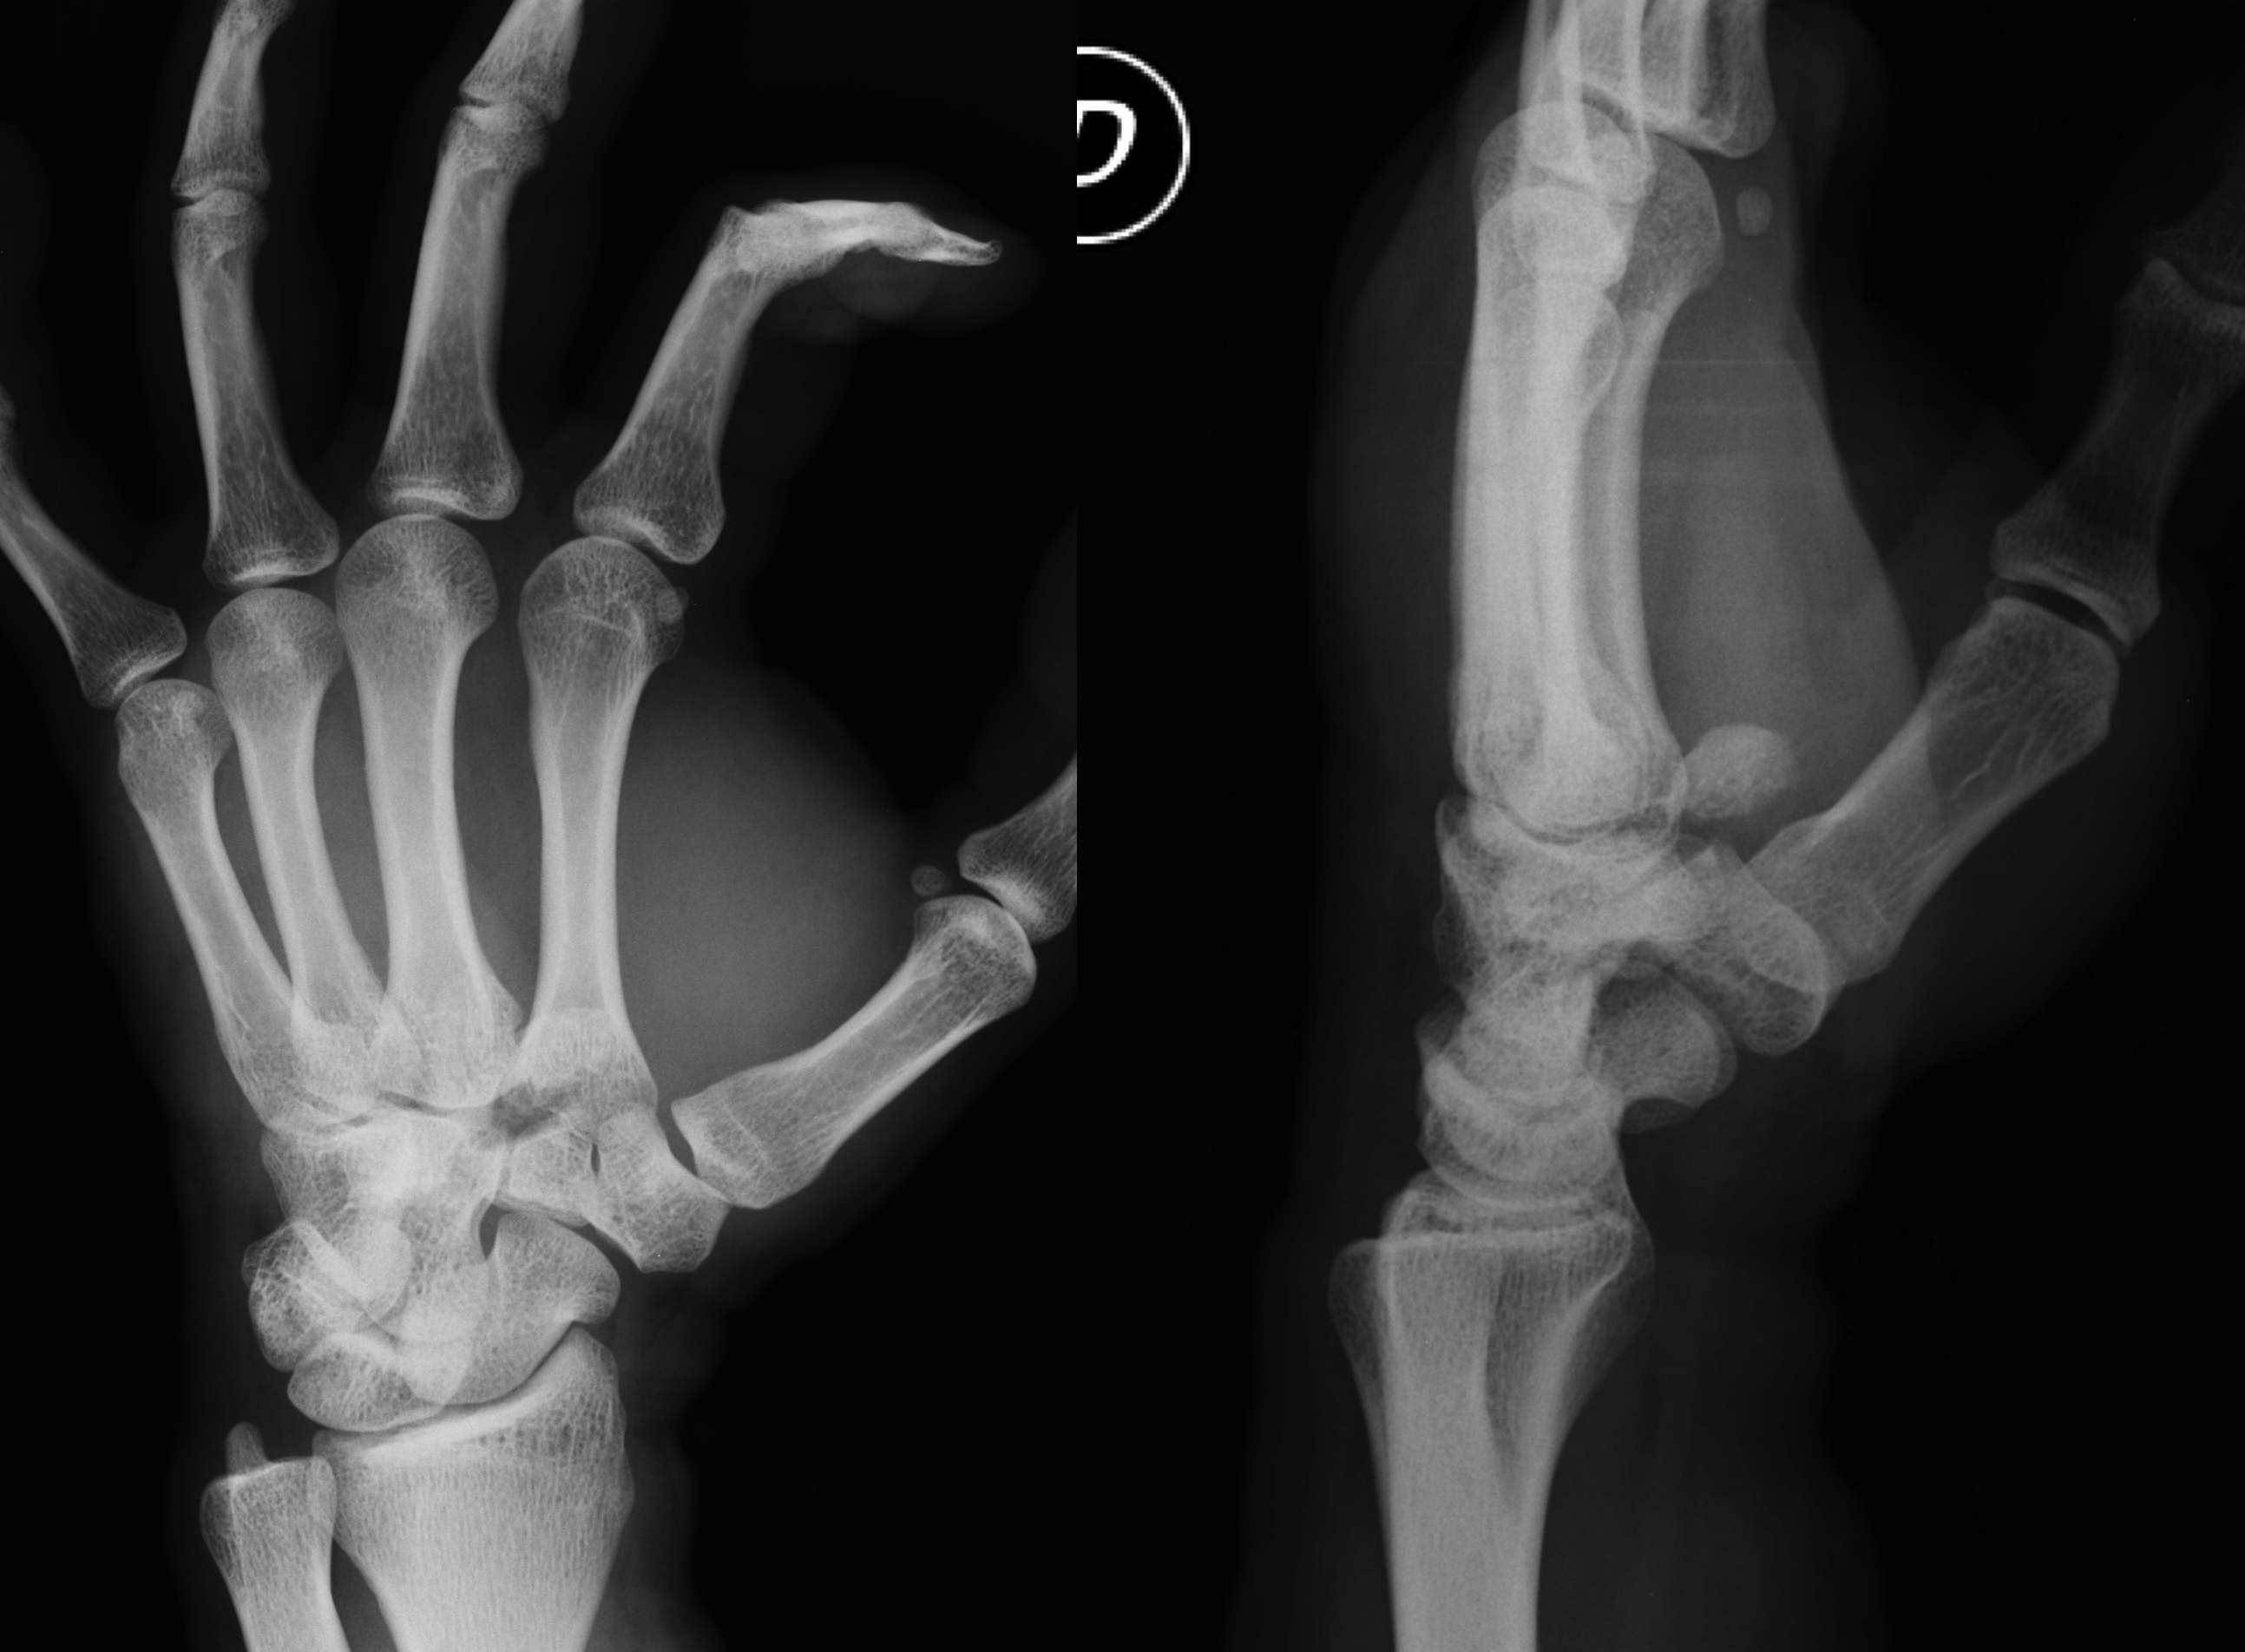

Fractura del cóndilo cubital de la base del 2do metacarpiano con desplazamiento a palmar. Presentación de un caso